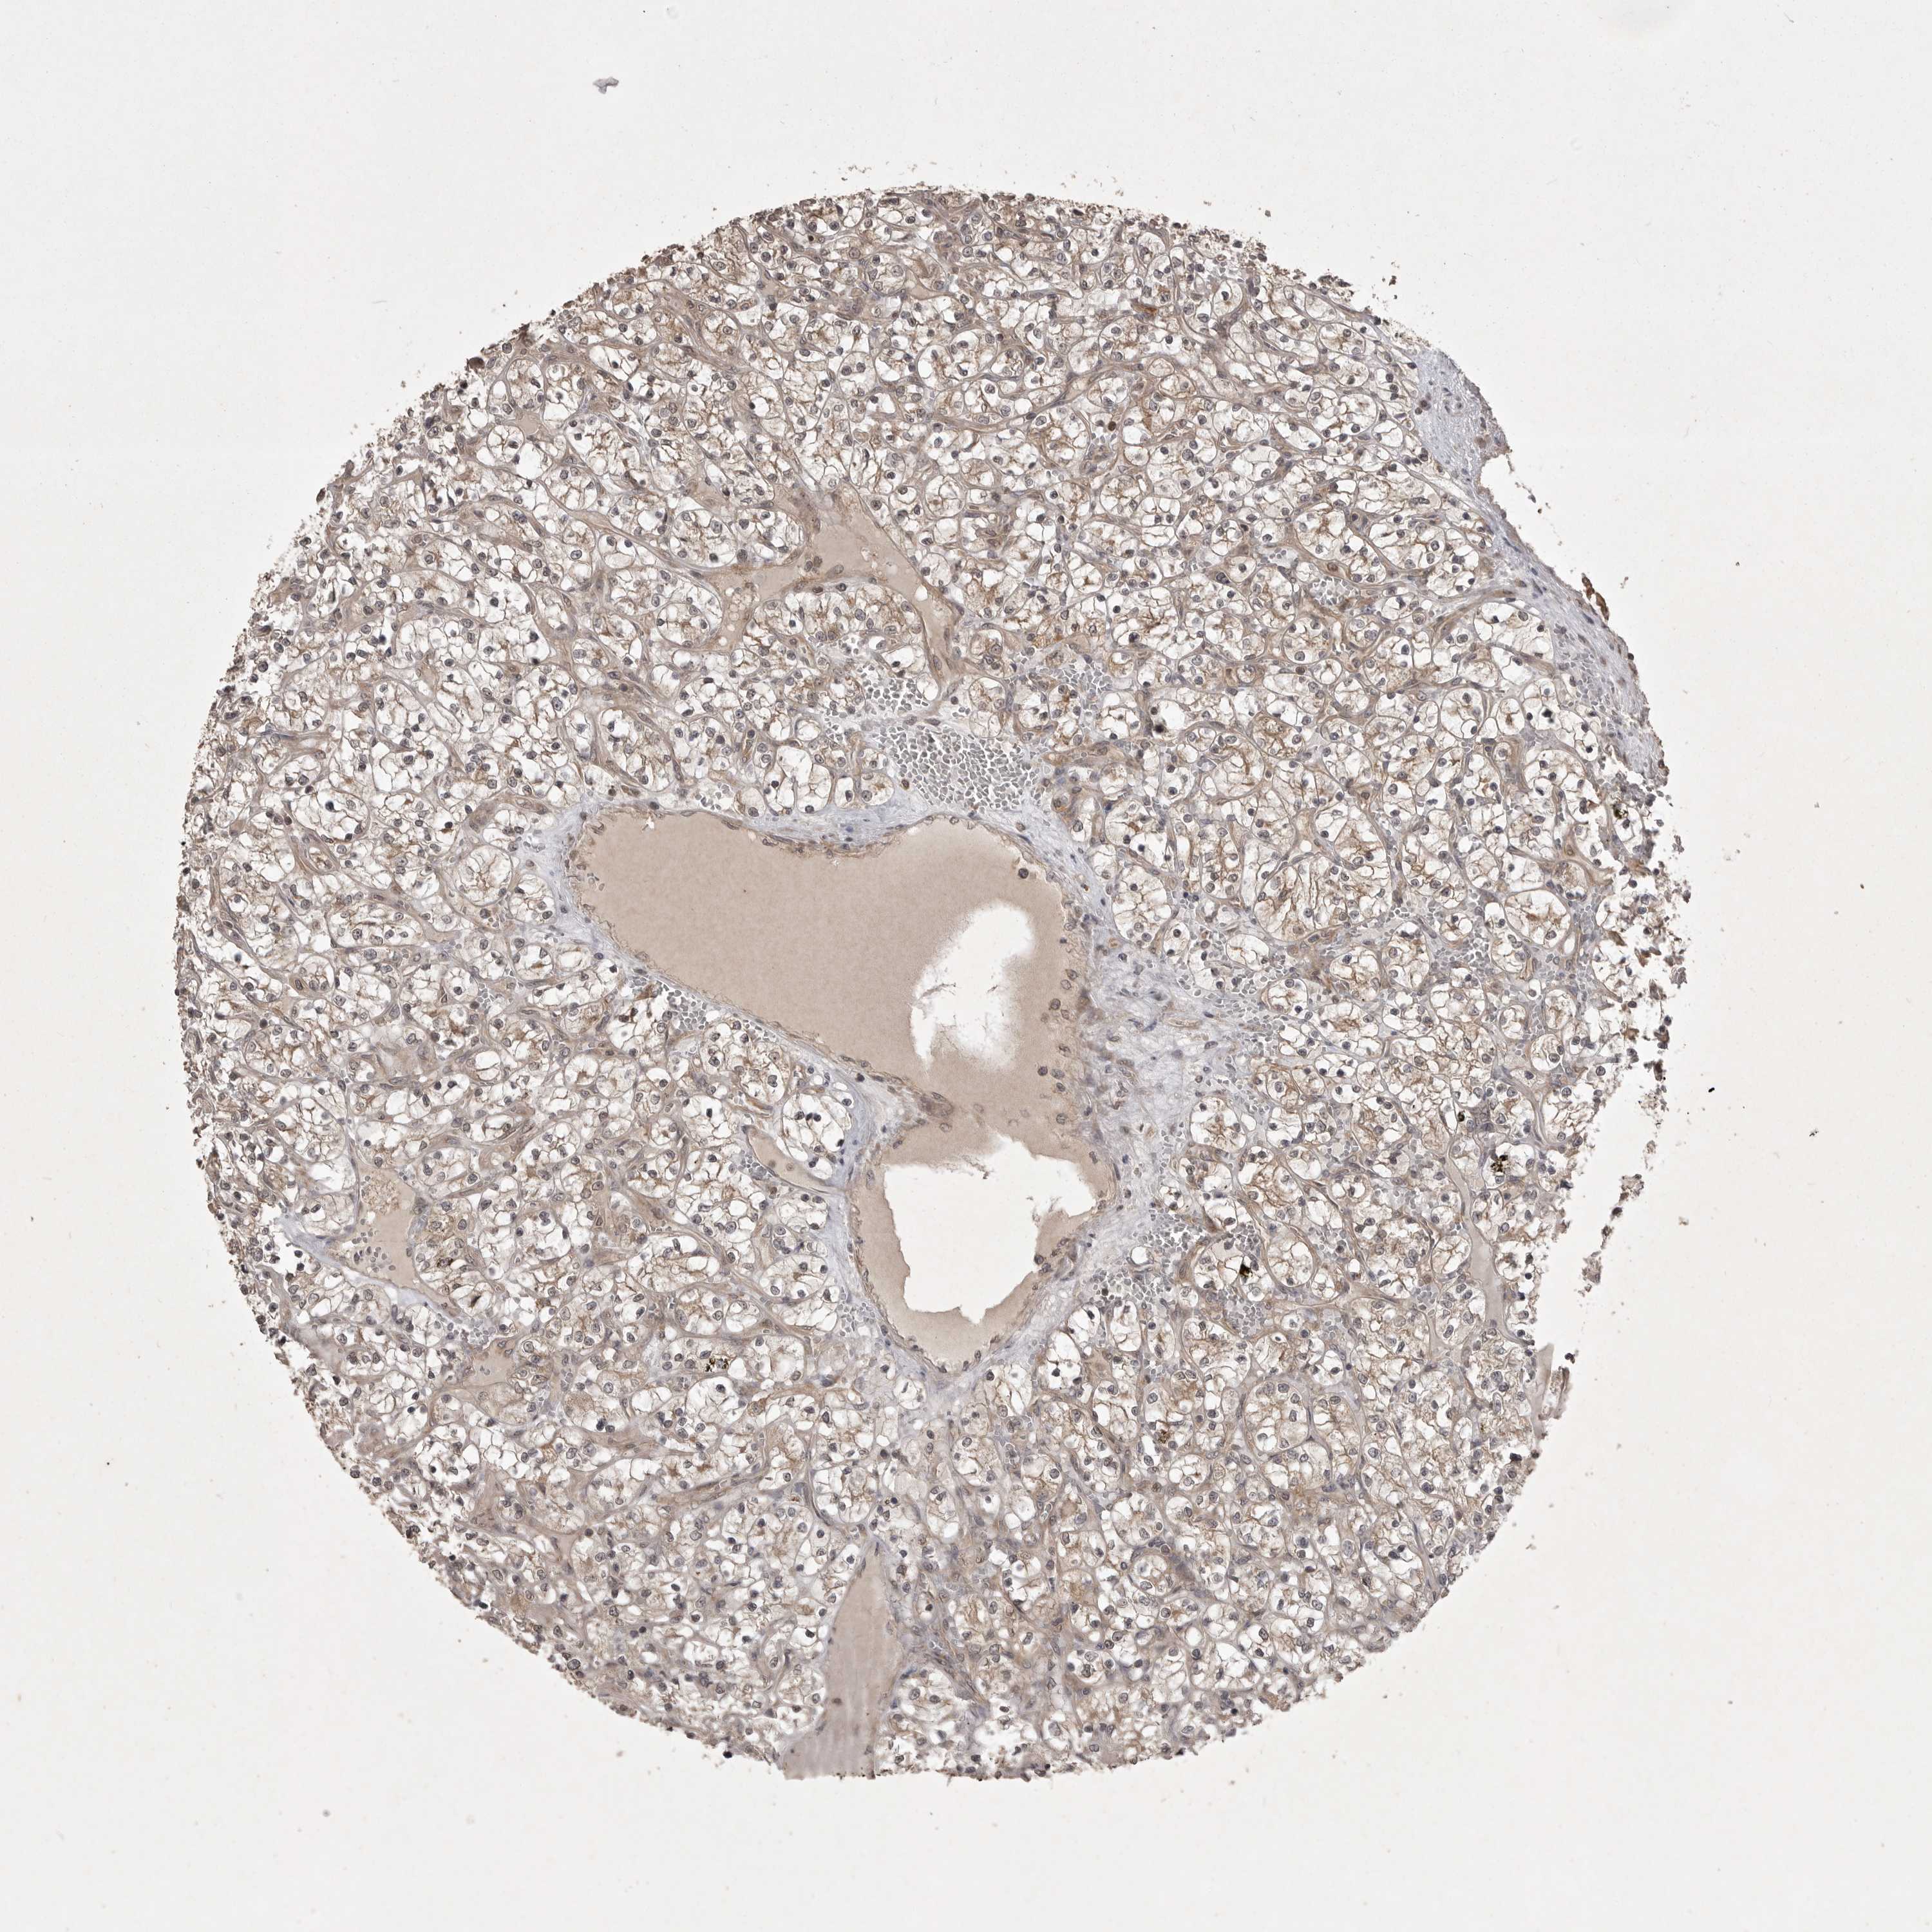

CANCER RENAL CANCER Show tissue menu

KICH TCGA KIRC TCGA KIRC VALIDATION KIRP TCGA PROTEIN RCC CPTAC PROTEIN EXPRESSION